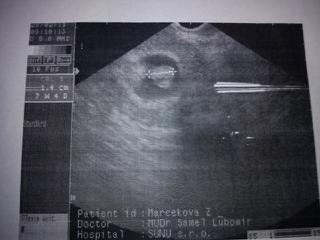

no konecne mozem pridat aj ja moju fotecku zo sona....sice moj doktor nedava foto, vytlacil mi to len cez tlaciaren, takze kvalita nie je moc dobra, ale ja sa vytesujem aj z takej fotky....ved krasna pamiatka...pri synovi take nieco vobec nebolo.....takze bolo to pondelok 28.2. a je to 7tt + 4 a mame 1.4 cm.....v profile mam, ze som v 9 tt, ale podla sona to bude neskor.....upravim zmeny, az ked budem vediet na 100%